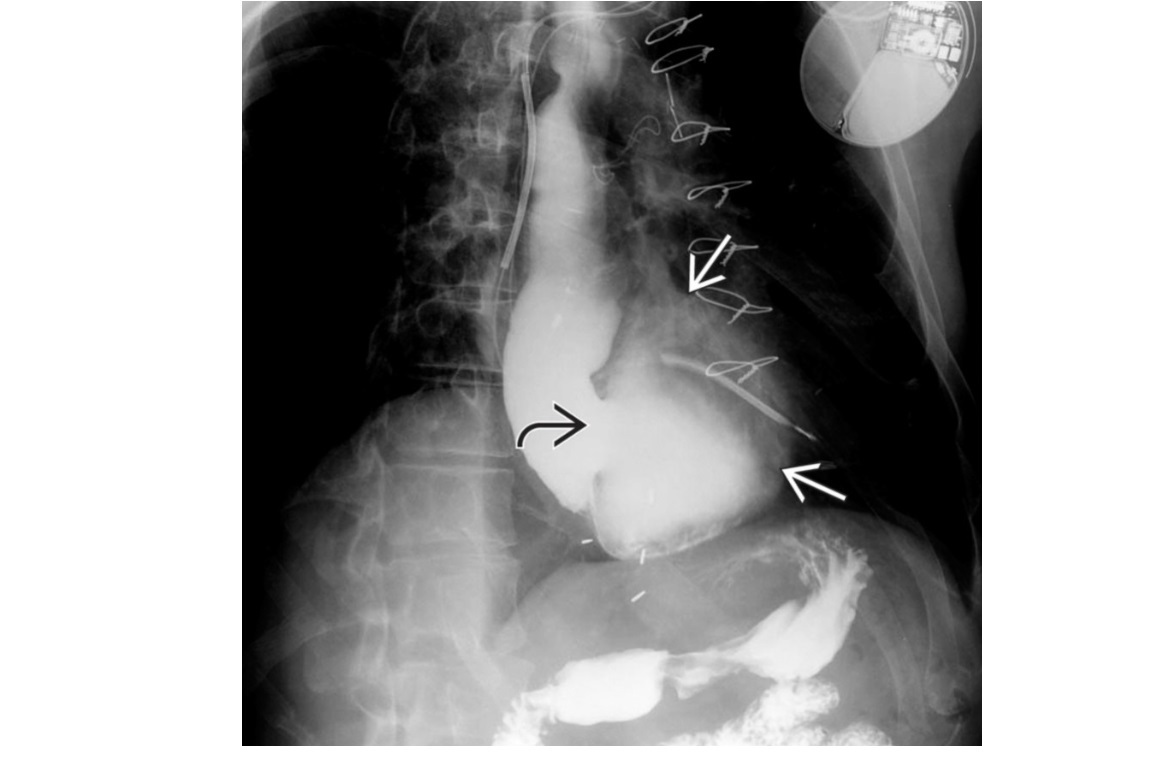

Epiphrenic diverticulum

Large saccular outpouching just above the diaphragm, right side

Can be mistaken for paraesophageal hernia - usually in on the left

associated with dysmotility disorders